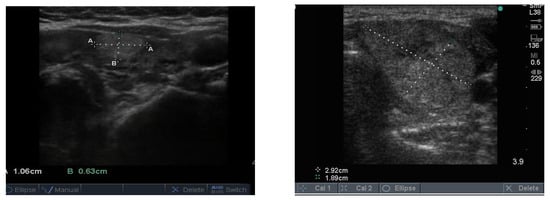

Follicular nodules are much less common than colloid nodules with a different appearance on ultrasound; they are more cellular, giving a solid appearance, with a whitish colour, i.e., less hypoechoic. They too have a sharp edge and halo and grow slowly over time []. The problem with these lesions is that FNAB is unable to differentiate between a benign follicular adenoma and follicular cancer, and if the latter is suspected, thyroid surgery is the final arbitrator. About 10% of benign thyroid nodules are follicular, and most of them end up being removed. Two examples of follicular nodules that were finally proven to be benign are shown in Figure 4. On follow-up ultrasound (US), 6–12 months later, repeat biopsy might be indicated if a nodule has grown by 20% or more in two or more dimensions; benign nodules also grow, but less quickly.

Figure 4.

Two examples of follicular nodules that were shown at surgery to be benign. The nodules are roughly oval shaped, slightly hyper echoic and have sharp edges and, particularly, the bigger of the two, thick halos.